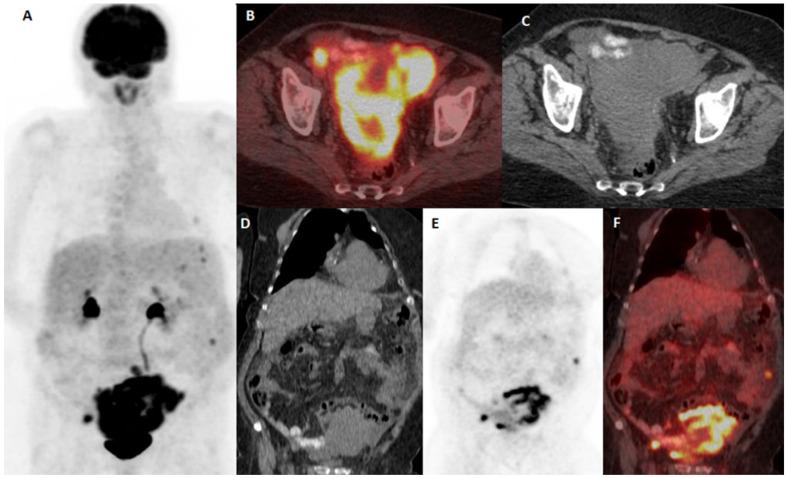

The global increase in the incidence of malignant melanoma, without significant changes in the mortality rate, may be influenced by the changes in the diagnostic approach and criteria, and the impact of innovative therapies on the survival of patients. Advances in treatment options, influencing prolonged survival, are bringing up a strong need for close surveillance of melanoma patients. In this observational, retrospective, and single-center study, we determined the impact of 18F-FDG PET/CT diagnostics on the outcomes and survival of malignant melanoma patients at different stages from an extensive and unselected group in a real-life clinical management setting. A total number of 189 malignant melanoma patients who underwent 18F-FDG PET/CT examination in the course of the treatment at one university oncology institute during the period from January 2010 to December 2024 were included in the study, and the multifactorial impact on the outcome and survival of malignant melanoma patients was observed in regard to the differences resulting from the therapeutic approaches and the introduction of new therapeutic options and drugs. Our results indicate that 18F-FDG PET/CT is a sensitive imaging tool for the detection of predominantly distant metastases in malignant melanoma patients belonging to an extensive and unselected population in a real-world clinical setting, not only at advanced melanoma stages but also at early stages of high-risk patients' surveillance. Follow-up appears to be of substantial importance for patients at advanced stages, but also for patients at early stages of disease, in particular in the presence of a strong clinical suspicion. Immunotherapy and combined therapy are improving overall survival in melanoma patients in real-world circumstances and equivalent clinical surroundings.

全球恶性黑色素瘤发病率上升,但死亡率无显著变化,这可能受到诊断方法和标准的改变以及创新疗法对患者生存影响的影响。治疗选择的进步延长了患者生存期,这使得对黑色素瘤患者进行密切监测的需求日益强烈。在这项观察性、回顾性单中心研究中,我们在真实临床管理环境下,从一个广泛且未经过筛选的群体中,确定了18F-FDG PET/CT诊断对不同阶段恶性黑色素瘤患者的治疗结果和生存情况的影响。本研究纳入了2010年1月至2024年12月期间在一所大学肿瘤研究所接受治疗过程中进行18F-FDG PET/CT检查的189例恶性黑色素瘤患者,并观察了治疗方法以及新治疗方案和药物的引入所导致的差异对恶性黑色素瘤患者治疗结果和生存情况的多因素影响。我们的结果表明,18F-FDG PET/CT是一种敏感的成像工具,不仅在晚期黑色素瘤阶段,而且在高危患者早期监测阶段,都能在真实临床环境中检测出广泛且未经过筛选人群中恶性黑色素瘤患者的主要远处转移。随访对于晚期患者以及疾病早期患者似乎都至关重要,特别是在临床高度怀疑的情况下。在真实世界和等效临床环境中,免疫疗法和联合疗法正在改善黑色素瘤患者的总生存期。